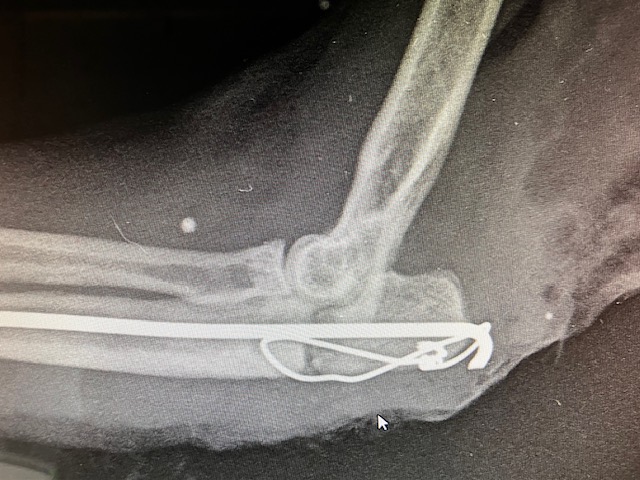

Nous utilisons exactement la même technique mais avec du matériel plus résistant. Nous augmentons le calibre de la broche et nous utilisons aussi un fil métallique de cerclage de diamètre plus important. En fin d’intervention, la réduction est satisfaisante.

la broche utilisée étant de diamètre plus important, nous n’avons pas pu la faire pénétrer dans toute la cavité médullaire de l’os ulnaire. Mais cela semble suffisant, nous voulons maintenant une résistance accrue. Pour compléter, l’intervention, nous pososn une contention externe complémentaire, avec une immobilisation du coude et de l’avant bras sous résine.

Un suivi radiologique est mis en place, avec un cliché toutes les 3 semaines. Cette fois, le montage tient correctement, on voit la cicatrisation osseuse progresser, le trait de fracture radio-transparent disparait.